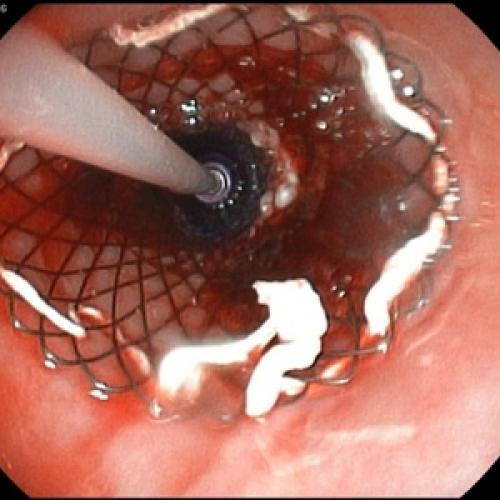

Пациентам с предположительным клиническим диагнозом острого панкреатита показано выполнение ЭГДС (дифференциальный диагноз с язвенным поражением гастродуоденальной зоны, осмотр БДС).

Отсутствие эффекта от проводимой анальгетической и спазмолитической терапии в течение 12-48 часов, быстро прогрессирующая желтуха, отсутствие желчи в ДПК при ЭГДС, признаки билиарной гипертензии по данным УЗИ свидетельствуют о стеноза терминального отдела холедоха (вклиненный конкремент БДС, папиллит). В этом случае показано проведение ЭПСТ. При остром панкреатите ЭПСТ производится без ЭРХПГ!